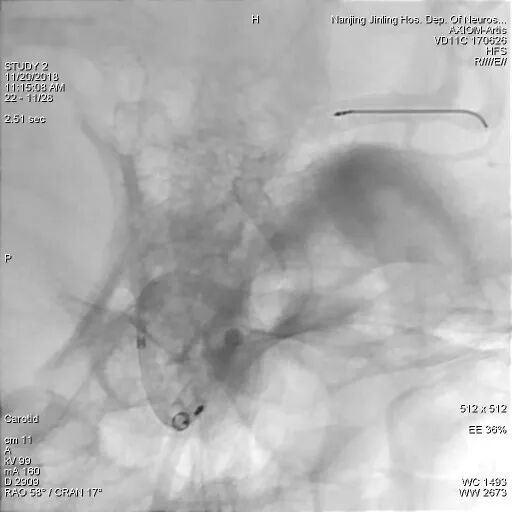

选取合适工作角度后,Marksman在Synchro 14微导丝引导下通过瘤内成袢技术超选至左侧大脑中动脉M2段,由于Synchro微导丝支撑力不够,无法将Marksman输送更远,则更换为PT导丝,将Marksman超选至左侧大脑中动脉M3段。

Marksman超选至左侧大脑中动脉M3段

Pipeline Flex在送至瘤颈口处时,因瘤腔巨大,支撑力不足,微导管多次疝入瘤腔内,术者随即尝试将Navien上高通过瘤颈,但多次尝试后因远端血管扭曲而失败。

随后术者决定使用球囊锚定微导管技术,从左侧股动脉穿刺置管上球囊,经右侧颈内动脉A1段,通过前交通动脉到达左侧大脑中动脉M1段,同时新的Marksman也超选到左侧大脑中动脉M2段。

为什么要用到微导管张鑫教授:“球囊锚定微导管辅助到位”技术在Pipeline Flex治疗复杂动脉瘤手术中的应用_https://www.jmylbn.com_新闻资讯_第5张

球囊经对侧A1和前交通,置于M1